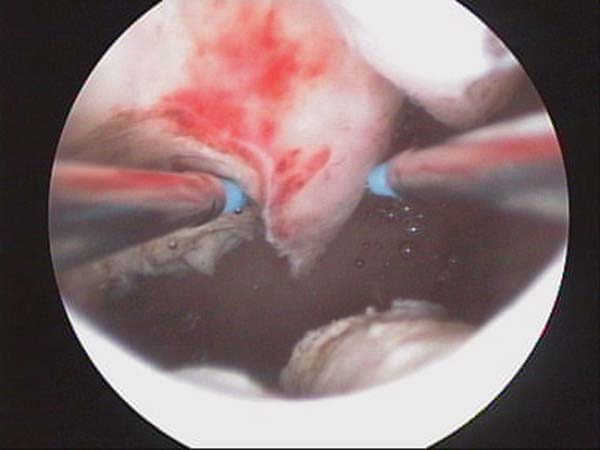

- Photos de l’hystéroscopie

Photos de l’hystéroscopie | Dr N Layyous